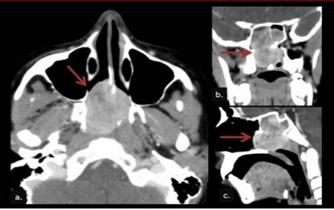

Exámenes

En laboratorio los parámetros suelen ser normales, con excepción de la elevación del VSG y PCR. Se deben realizar cultivos del drenaje del canal auditivo, o granulaciones, y enviarlos para tinción de Gram y cultivo para bacterias. También deben enviarse tinciones y cultivos para hongos. En imágenes la TEM y la RMN pueden ser útiles tanto para el diagnóstico (se observaría erosiones del hueso temporal) como para el seguimiento.